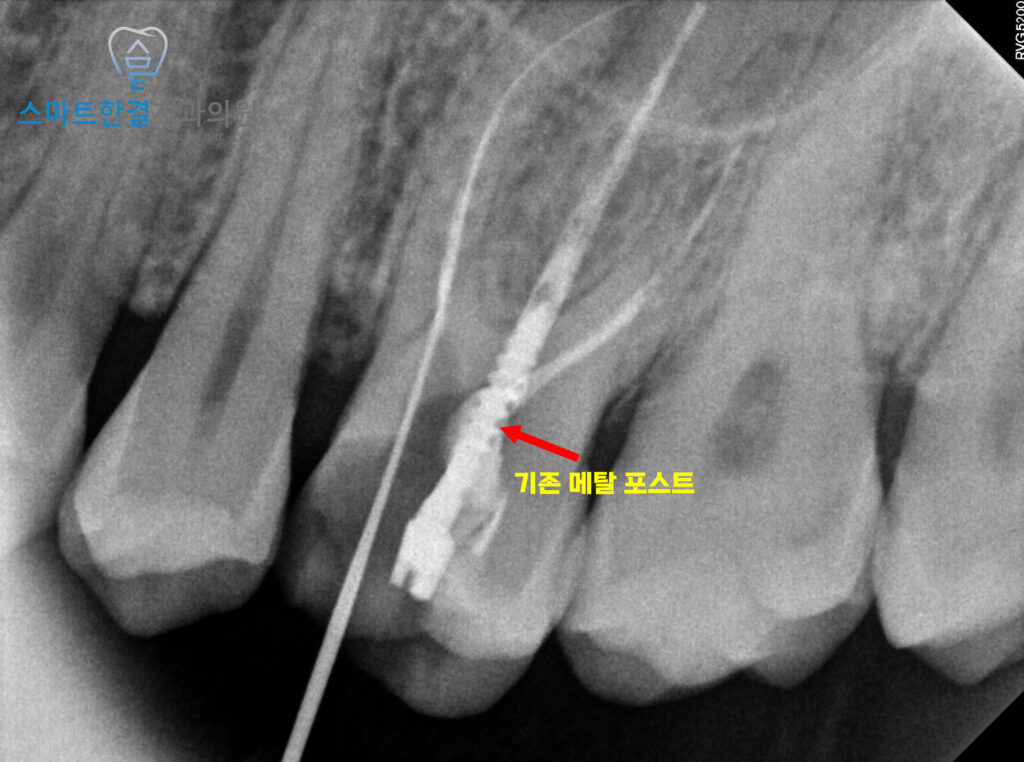

기존 치료 시 메탈 포스트를 활용하여

신경치료가 이루어졌으나,

염증이 발생한 근관이 아닌

다른 근관에 포스트가

삽입된 상태였는데요.

이를 통해 염증이 있는 부위에

접근할 수 있다고 판단하여,

우선적으로 재신경치료를 진행하기로 했어요.